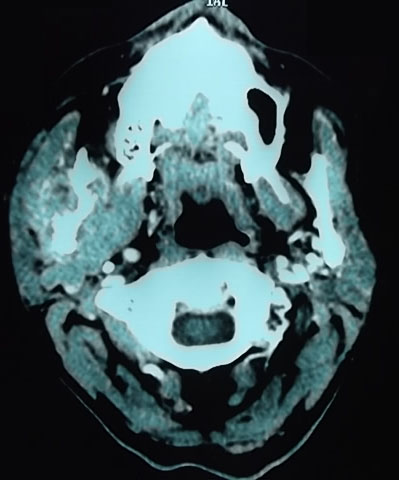

L'articulation temporo-maxillaire est une localisation métastatique rare. Le primitif est classiquement prostatique ou mammaire. La localisation pulmonaire étant rare. Le type histologique le plus fréquemment est l'adénocarcinome. Le carcinome pulmonaire à petites cellules avec métastase mandibulaire est exceptionnel. Nous rapportons l'observation d'un patient âgé de 62 ans, tabagique à 40 paquet/année, admis pour une altération récente de l'état général évoluant depuis 1 mois. A l'examen, il avait une tuméfaction de consistance dure temporo-mandibulaire droite. L'examen respiratoire trouvait des râles ronflants aux 2 champs pulmonaires et un hippocratisme digital. Au bilan biologique, il y avait une VS à 55mm, une fibrinémie à 6,94g/l, une CRP à 25mg/l et une cholestase hépatique anictérique. L'échographie des parties molles de la tuméfaction faciale avait montré une masse tissulaire avec ostéolyse du Ramus mandibulaire. Le scanner du massif facial avait trouvé une lésion tissulaire lytique, d'allure secondaire, hypervasculaire, mal limitée, hétérogène, centrée sur la branche montante droite de la mandibule, étendue au condyle, mesurant 32x37 mm et envahissant les muscles masséters et ptérygoïdien. Le scanner thoraco-abdominal avait montré 2 masses tissulaires spiculées du lobe pulmonaire supérieur droit d'allure primitive, mesurant 30x18 mm. Il y'avait 2 lésions hypodenses hétérogènes intéressant les segments IV et VII du foie respectivement de 24 et 54 mm de grand axe. La biopsie pulmonaire scanno-guidée avait conclu à un carcinome neuroendocrine, à petites cellules, primitif pulmonaire. Le diagnostic de cancer pulmonaire avec métastases hépatiques et mandibulaire a été retenu. Le patient a été adressé en carcinologie médicale pour radio et chimiothérapie.